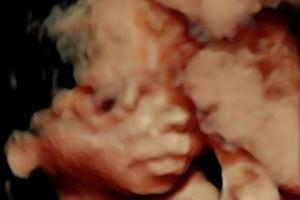

Ratgeber Schwangere Pippa Middleton: Im Blumenkleid zur royalen Hochzeit Pippa Middleton hat sich für die Hochzeit von Meghan Markle und Prinz Harry in Schale geworfen. Unter ihrem Kleid wölbt sich bereits ein ...